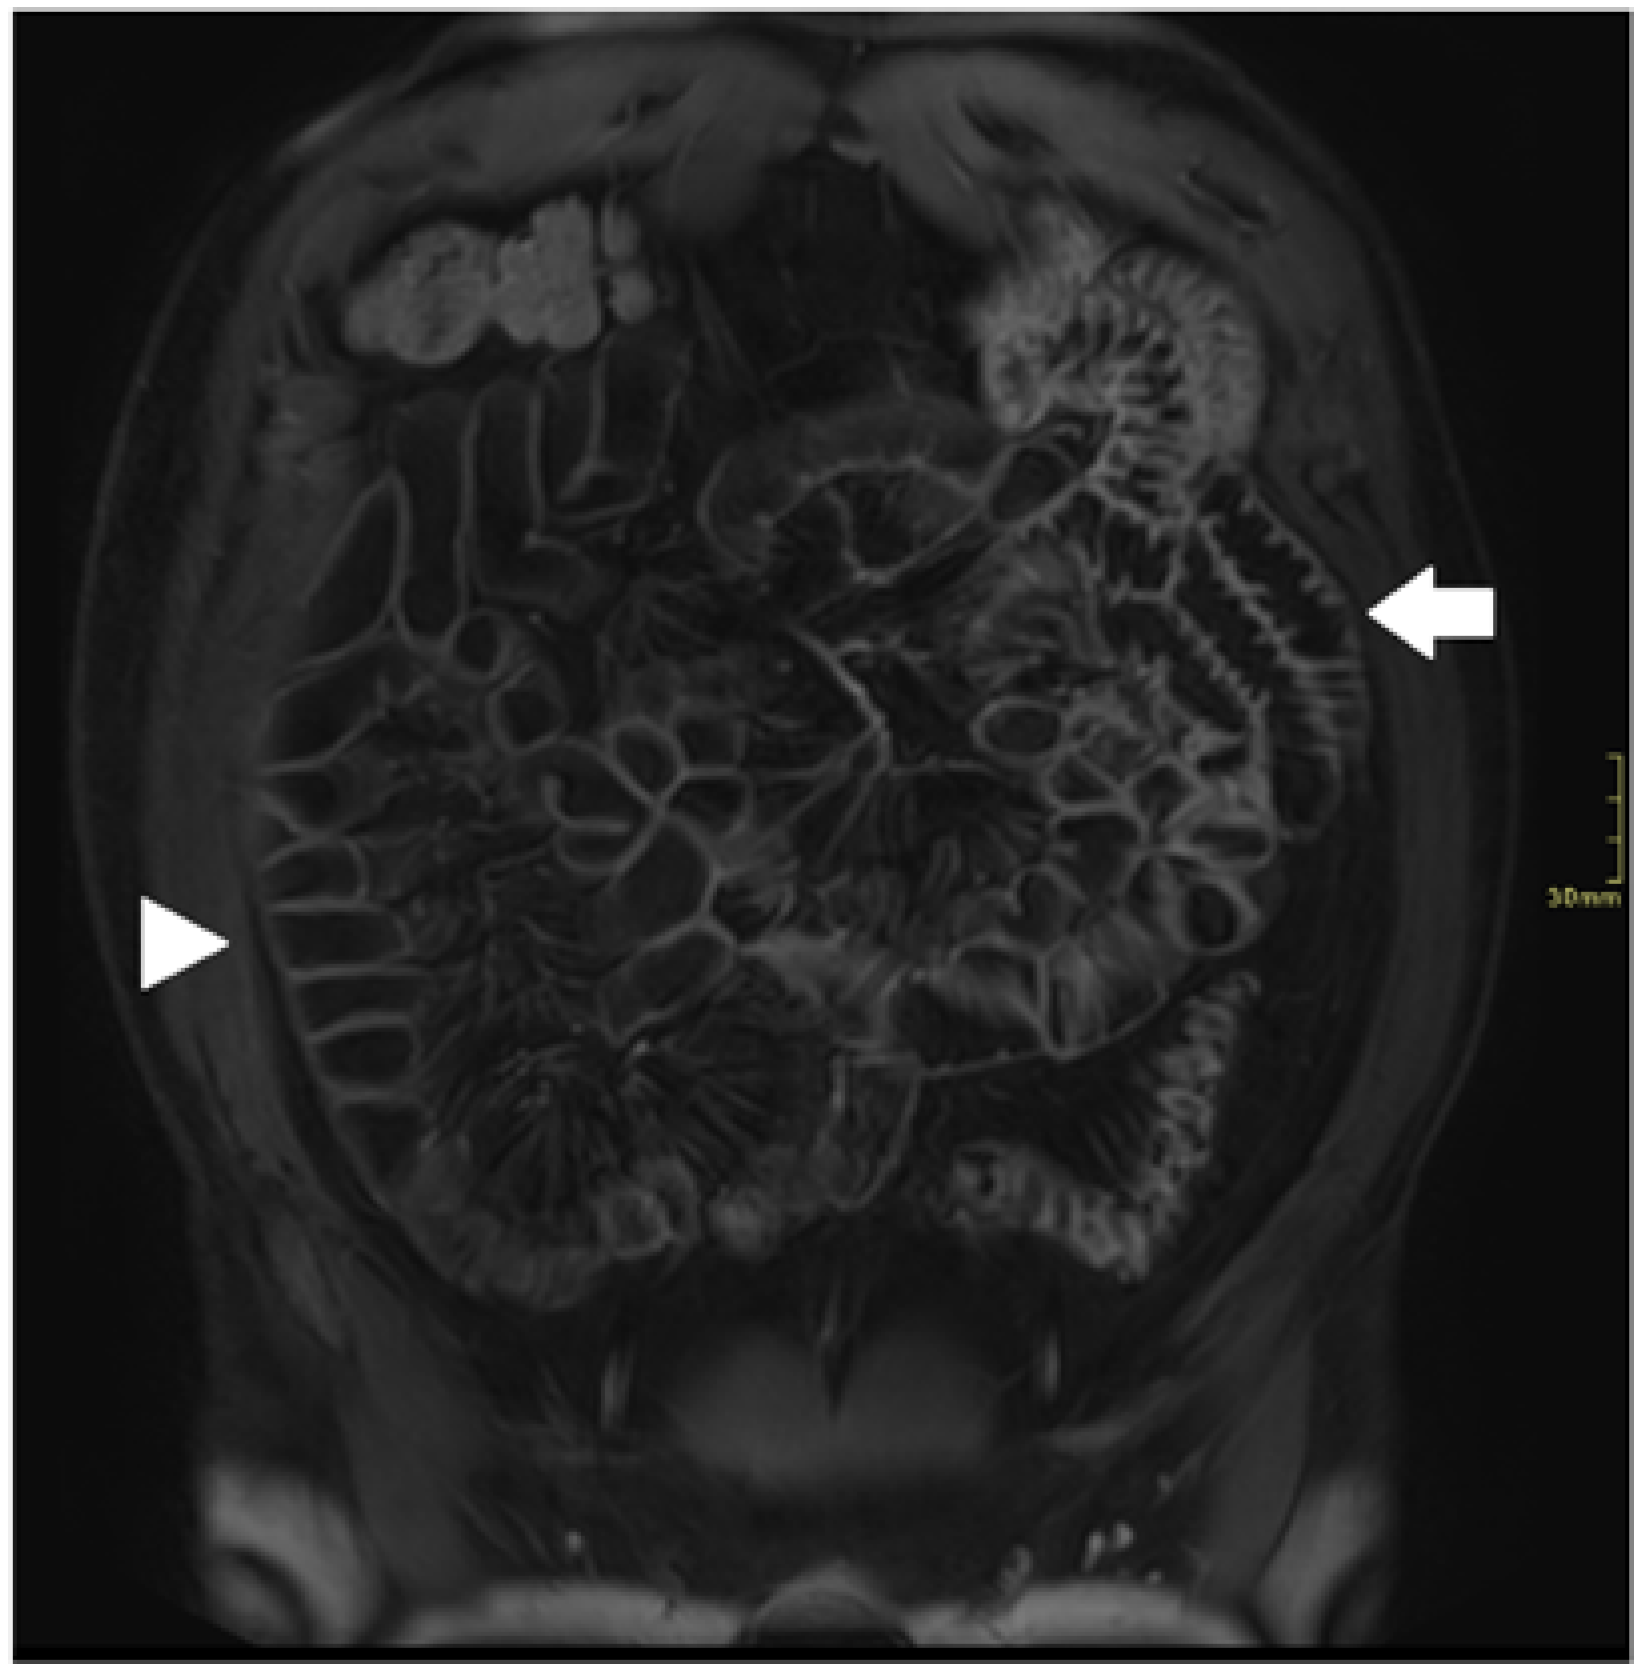

3. Motion Artifact

5. Bowel Distention